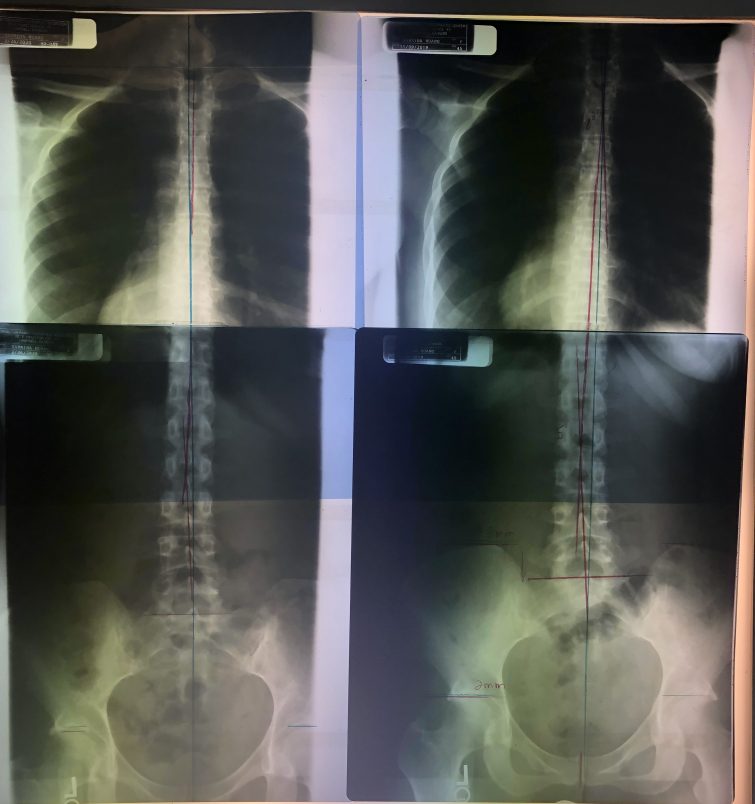

From the backside view, the Right side is three months ago and the Left is after (the blue line is where the center should be, the red show how much my spine was off the center, especially, on the lower back).

我是去年11月開始的, 12月回臺灣一個月, 然後今年的一月和二月, 每週三到四次的整脊, 可能我本身的健康狀況還不錯吧, 所以第一個月結束時並沒有很大明顯的轉變, 但是睡眠似乎有好一些, 然後我就回台灣了, 但是當我從台灣回來後, 很多朋友都說我瘦很多 (可是我也沒有運動, 在台灣的飲食你也知道, 完全沒在控制), 回美後又開始每週三到四次的整脊, 一月後我就開始早上會想排便, 雖然沒有每天, 但是一週有三四天也算是很大的進展, 然後開始覺得有精神, 情緒也變得穩定很多 (開始冥想打坐也有幫助), 然後二月又過去了, 終於到了要再拍脊椎X光片, 看看三個月的成效, 結果我的頸椎從負五度變成正25度 (雖然離健康的正45度還有一點距離), 胸椎和頸椎也非常接近正常的位置, 醫生比我還高興, 他們蠻驚訝我頸椎的進步程度 (該做的脊椎運動我都沒有乖乖做, 所以這樣的結果我很滿意了).